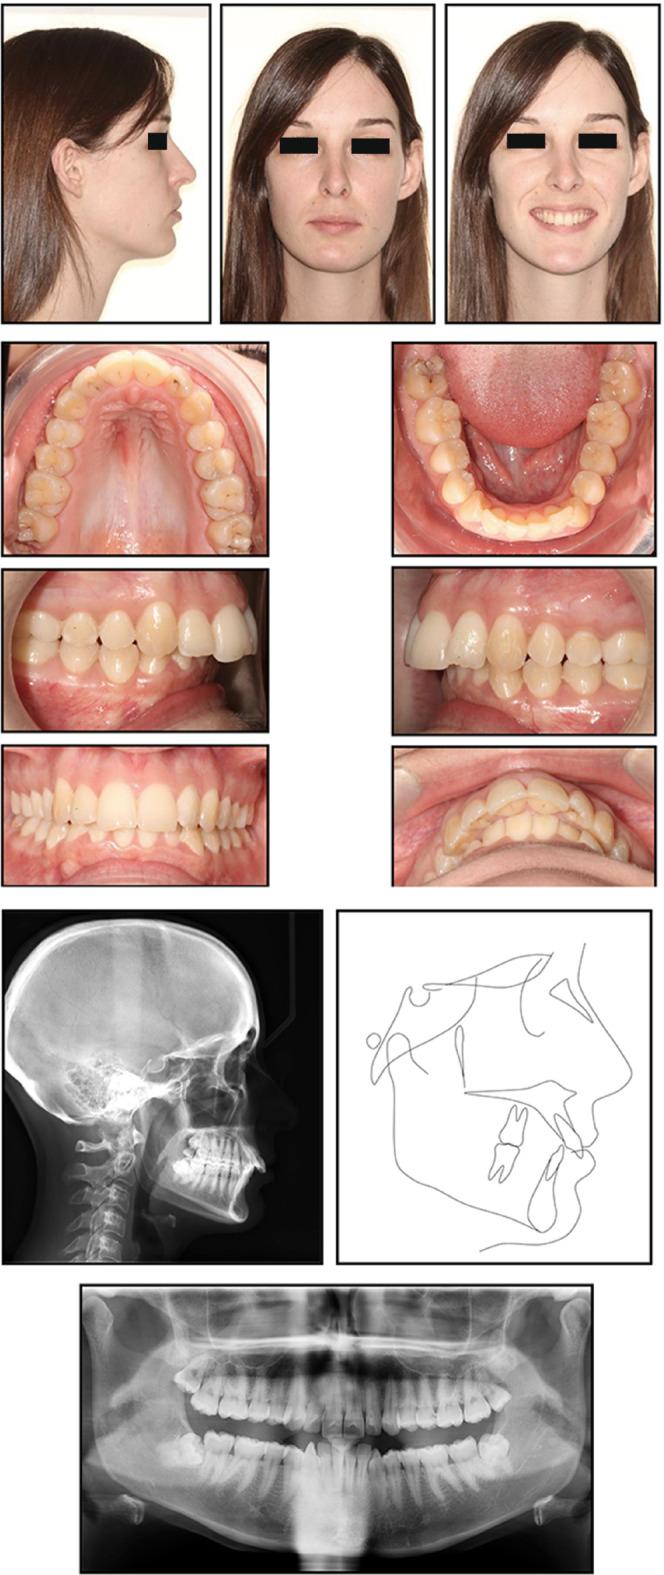

To describe an esthetic orthodontic treatment using aligners in an adult patient with dental class II malocclusion associated with crowding. A 25-year-old female patient with skeletal class I, bilateral class II relation, increased overjet and overbite and crowding in both arches presented for orthodontic treatment. The patient refused conventional fixed multibracket treatment in favor of aligners. Pre- and post-treatment records are presented. Treatment objectives were achieved in 10 months, and the patient was satisfied with the functional and esthetic outcomes. Combining aligners with appropriate attachment location and geometry is an efficacious means of resolving orthodontic issues such as class II malocclusion in a time frame comparable to that of conventional fixed orthodontics. Staging in distalization increases the predictability of movement. Furthermore, this system is associated with optimal oral hygiene and excellent esthetics.

描述在一名患有伴有牙列拥挤的安氏II类错牙合的成年患者中使用隐形矫治器进行的美学正畸治疗。一名25岁女性患者,骨骼I类,双侧安氏II类关系,覆盖和覆牙合增加,上下牙弓均有拥挤,前来接受正畸治疗。患者拒绝传统的固定多托槽治疗而选择隐形矫治器。展示了治疗前和治疗后的记录。在10个月内实现了治疗目标,患者对功能和美学效果感到满意。将隐形矫治器与合适的附件位置和几何形状相结合,是在与传统固定正畸相当的时间范围内解决诸如安氏II类错牙合等正畸问题的有效方法。远中移动分阶段进行可提高移动的可预测性。此外,该系统有助于保持最佳的口腔卫生并具有出色的美学效果。